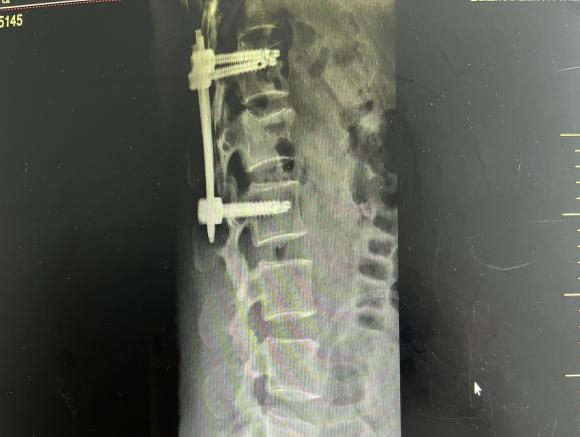

4月23日,贵州航天医院第58次晨读会由我院骨科副主任医师张艳金作学术交流,他以“加速康复指导下的快速手术”为题,详细讲解了老年股骨粗隆间骨折与儿童四肢骨折的临床诊疗难点,结合加速康复外科(ERAS)核心理念,重点阐述了ERAS理念在两大人群中的创新实践,实现患者入院后6至24小时内即可接受手术治疗。针对老年髋部骨折患者,提出通过多学科协作(MDT)与微创手术优化围术期管理,在确保安全前提下缩短术前等待时间,实施精准化麻醉及术后康复方案,可有效降低并发症发生率、改善患者生活质量和预后效果。在儿童骨折领域,强调微创术式与心理干预并行的双轨策略,既减少手术创伤对骨骼发育的影响,同时关注患儿心理疏导,实现生理功能与心理健康同步康复。并通过典型案例的影像学资料与随访数据,直观展示了ERAS理念指导下骨科治疗模式的创新成果。 贵州航天医院骨科 专家简介 赵学平 中共党员,骨科党支部书记、主任,主任医师 临床擅长:从事骨科临床工作30余年,对骨科常见疾病的诊治具有丰富的临床经验。 世界中医药联合会脊柱康复专业委员会常务理事,中华中医药学会整脊分会常务委员,中国中西医结合学会骨伤科分会肢体矫形功能重建与康复专家委员会常务委员,中国研究性医院学会骨科创新与转换专业委员会关节外科学组保髋工作委员会常委,中国康复技术转化及发展促进会骨外科与康复技术转化专业委员会常务委员,泛珠三角区域运动医学联盟(PPRD-SMA)理事会常务理事,中国研究型医院学会运动医学专业委员会委员,贵州省中医药学会整脊分会副主任委员,贵州省中西医结合学会银质针专业委员会副主任委员,贵州省康复医学会骨与关节专业委员会常务委员,贵州省人民医院骨科专科联盟常务理事,贵州省康复医学会骨内科专业委员会常务委员,中华医学会贵州省骨科学会委员,贵州省康复医学会脊柱脊髓专业委员会常务委员,贵州省运动医学分会委员,贵州省康复医学会骨与软组织肿瘤专业委员会委员,遵义市医学会创伤分会副主任委员,贵州省康复医学会骨内科专业委员会遵义地区分会常务委员,遵义市医疗事故鉴定、伤残鉴定、工伤鉴定、司法鉴定专家。 长期从事骨科临床研究及教学工作,在国家级、省部级杂志发表论文20余篇,SCI论文2篇,参与主编骨科专著2部,主持省部级科研项目2项,参与指导省部级、市级科研项目6项。 陈明勇 骨科副主任,副主任医师 临床擅长:从事创伤骨科工作约20年,对骨缺损、骨不连、骨肿瘤、肢体畸形等的肢体矫形重建及功能重建,慢性化脓性骨髓炎的根治治疗、糖尿病足的保肢治疗、快速康复理念(ERAS)下的老年骨折的诊治,四肢复杂骨折的诊治,四肢骨折等微创手术治疗具有丰富的临床经验。 2004年毕业于遵义医学院临床专业,曾在中国人民解放军总医院、广西医科大学第一附属医院、上海第六人民医院骨科进修。中国中西医结合学会骨伤科专业委员会横向骨搬移治疗糖尿病足及微血管网再生学组首届委员,遵义市医学会创伤分会常务委员。 瞿 辉 中共党员,骨科副主任医师 临床擅长:对骨科的常见病、关节外科、脊柱外科及运动医学疾病的诊治具有丰富的临床经验,熟练掌握骨科手术操作技术。 毕业于遵义医学院临床医学系,2005年前往广州中山大学第一附院骨显微医学部进修学习,2011年前往成都华西医院进修学习,并多次在省内外学习骨科相关知识,是中华医学会骨科分会会员。 赵兴东 骨科主任医师 临床擅长:擅长骨科的常见病及各种创伤、四肢骨折创伤修复、骨感染、手足疾病的诊治和手足体表畸形的矫形整复,熟练掌握骨科四肢骨病及创伤的手术操作技术,尤其在四肢关节复杂性损伤、手足外伤、组织缺损创面、难治创面的皮瓣修复方面及平足、高弓足矫形方面及四肢慢性疼痛诊治、康复方面具有丰富的临床经验。 硕士研究生,毕业于遵义医学院临床外科系,2015年前往山东省立医院手足外科进修学习;遵义市医学分会创伤分会第一、二届委员,遵义市手外科医学会第二委届员会常务委员;在省级及省级以上期刊发表文章9篇,参编著作2部,参与主持并完成市级课题1项,参与市级课题2项、省级课题1项。 张艳金 中共党员,骨科副主任医师 临床擅长:从事骨外科工作16年,对复合伤、多发伤的救治、四肢骨干骨折、关节周围骨折、骨肿瘤、骨髓炎等诊治具有丰富的临床经验。 中共党员,硕士研究生,2006年本科毕业于山西医科大学第二临床医学院,2011年研究生毕业于北京军区总医院;在“老年COPD患者合并髋部骨折的诊治”国际合作课题组研究两年,在老年髋部骨折的诊治方面具有丰富的经验,并发表论文6篇;主持遵义市级课题1项,承担遵义医科大学的临床教学工作,获得遵义医科大学优秀带教老师荣誉。编撰有《骨科疾病诊疗精粹》一书,开展2项新技术,编撰地方规范《务川自治县创伤骨科常见疾病诊疗规范》一书。 张俊凯 骨科副主任医师 临床擅长:从事骨科临床工作28年,对创伤骨折、骨感染、骨缺损、骨不连等外科诊治,四肢骨折的微创手术治疗,四肢复杂骨折(如关节内粉碎性骨折、多发骨折等)的损伤控制及手术治疗等具有丰富的临床经验。 1995年毕业于遵义医学院临床专业,2009年前往复旦大学附属医院骨科进修1年。 卢懿明 中共党员,骨科副主任医师 临床擅长:从事骨科工作18年,对创伤骨折、四肢骨折的微创手术治疗、四肢复杂骨折(如关节内粉碎性骨折、多发骨折等)的损伤控制及手术治疗,尤其是髋部骨折的PFNA等微创技术,踝关节骨折、膝关节周围骨折的Mipo微创技术等具有丰富的临床经验,开展了4项新技术,发明6项新型专利技术。 2005年毕业于遵义医学院临床专业,2017年,前往南方医科大学第三附属医院骨科进修半年,回院后运用Mipo技术对骨干骨折及干骺端骨折的治疗技术,同时积极开展骨盆骨折、髋臼骨折腹直肌外侧切口的应用;发表了多篇专业论文,经常参与省内外学术交流会授课,获得医院荣誉称号多个。 邬夏荣 骨科副主任医师 临床擅长:从事骨科工作16年,对四肢复杂骨折、骨肿瘤的诊治,尤其是足踝创伤、慢性踝关节损伤、平足症等诊疗具有丰富的临床经验。 2006年毕业于遵义医科大学临床医学专业,曾在陆军军医大学西南医院进修学习,发表多篇骨科学术论文。 余德怀 中共党员,骨科副主任医师 临床擅长:从事骨科工作10余年,对运动医学、骨关节、脊柱外科常见病、多发病的诊治具有丰富的临床经验。 硕士研究生,2011年毕业于遵义医学院临床医学专业,曾前往遵义医科大学附属医院运动医学专业进修学习;是贵州省医学会运动医学分会青年委员,西部关节镜联盟委员;发表多篇骨科学术论文。 冯 乾 骨科副主任医师 临床擅长:从事骨科工作近20年,熟练掌握骨科多发病及常见病的诊治,尤其对脊柱退变性疾病的诊断及治疗具有丰富的临床经验,主要研究脊柱微创相关治疗方式,能熟练开展椎间孔镜及UBE。 曾前往北京大学第三医院进修学习疼痛及椎间孔镜、首都医科大学友谊医院专业进修脊柱内镜;是贵州省康复医学会第三届脊柱脊髓专业委员会委员;发明专利3项、发表脊柱外科专业论文多篇。 赵小锋 中共党员,骨科副主任医师 临床擅长:从事骨科临床工作11年,对骨科常见病、多发病诊疗有较为丰富的临床经验,擅长脊柱相关疾病诊断及治疗,尤其是颈、腰、腿疼痛疾病诊断及治疗,擅长胸腰椎骨折微创经皮穿刺内固定术、经皮穿刺椎体成形术、经皮穿刺脊柱内镜下腰椎间盘摘除术、单纯开创腰椎间盘摘除术、腰椎滑脱复位椎间植骨椎融合内固定术、腰椎管狭窄减压融合内固定术及人工髋、膝关节置换术等。 2012年毕业于遵义医学院外科学专业硕士研究生,2019年参加“遵义市115医学人才精英计划”于上海交通大学第一附属医院培训学习,2023年于北京大学第三人民医院脊柱外科进修学习,曾获得遵义市优秀医师荣誉称号。 遵义市手外科第一届委员,遵义市医学会创伤分会第一届委员,遵义市医学会创伤分会第二届委员,贵州省康复医学会第三届脊柱脊髓专业会委员,遵义市医学会烧伤与整形外科学分会委员,发表论文5篇,其中国家级核心期刊1篇,SCI论文1篇,主持市级课题1项并结题,参与市级课题2项。 贵州航天医院骨科 简介 基本情况 贵州航天医院骨科组建于20世纪60年代,前身是以创伤和断肢(断指)再植闻名于世的上海市第六人民医院骨科,中国断肢(断指)再植的奠基者、中科院院士陈仲伟等著名专家、学者多次莅临科室指导医疗、教学,是贵州省最早拥有专业骨科技术科室之一,在70年代开展了贵州省首例断肢(断指)再植手术。组建50余年来,诊治患者已逾百万,挽救了无数的伤病员,成为了保障遵义地区人民群众健康的重要支撑。 经过几代人的不懈努力,今天的骨科,已由创伤骨科发展至骨病、骨肿瘤、骨结核等领域,现有脊柱外科、关节外科、四肢创伤、手足外科四个亚专科,成为了集医疗、教学、科研于一体的综合学科,是贵州省临床重点专科、遵义市临床重点专科、遵义市骨科临床医学中心、遵义市基层骨科专科联盟理事长单位。 科室目前开放床位110张,共有医护人员50余人,副高级以上专家18人,硕士研究生15人。拥有一流骨科医疗设备多台,每年不定期选派优秀技术骨干到全国各大知名医学院校进修、学习、参观、交流,并邀请国内、国外知名专家教授来院进行交流、指导,通过不断引进国内外先进的诊疗技术,科室医疗技术水平稳步提升,为广大人民群众提供了优质的医疗服务。 专科特色 骨一科 (一)骨缺损、骨不连的肢体与功能重建 胫骨横向骨搬移技术治疗糖尿病足: (二)慢性骨髓炎的根治治疗 (三)肢体缺血性疾病如糖尿病足、脉管炎的保肢治疗 (四)皮瓣修复 (五)复杂创伤的治疗 (六)老年髋部骨折及小儿骨折快速手术 老年髋部骨折: 骨二科 (一)胸腰椎骨折微创经皮椎弓根螺钉固定术 (二)老年性骨质疏松性患者腰椎滑脱脊柱内固定术(骨水泥螺钉) (三)V形双通道脊柱内镜技术(VBE)腰椎融合术治疗腰椎退行性疾病 (四)老年性骨质疏松性骨折(PVP/PKP)术 (五)人工髋关节置换术 (六)双侧股骨头坏死人工全髋关节置换 (七)右侧全髋置换术后假体周围骨折翻修 (八)人工膝关节置换术 (九)人工膝关节假体松动翻修 (十)关节镜技术 传统手术切口 关节镜技术切口 诊疗范围 骨一科 1.四肢创伤、矫形。 2.手、足踝外科。 骨二科 end